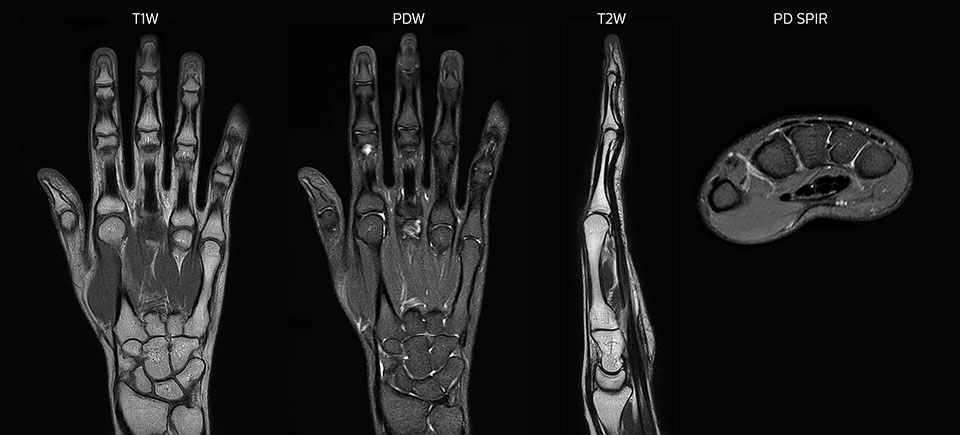

MRI of hand and wrist with large FOV

Prodiva imaging of the hand covers the fingertips and includes the full wrist as well. The dS MSK M coil is easy to use.